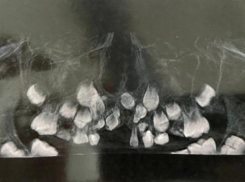

Общество Врачи Ростова помогли ребенку, у которого восемь лет не росли зубы

Это редкая челюстная аномалия